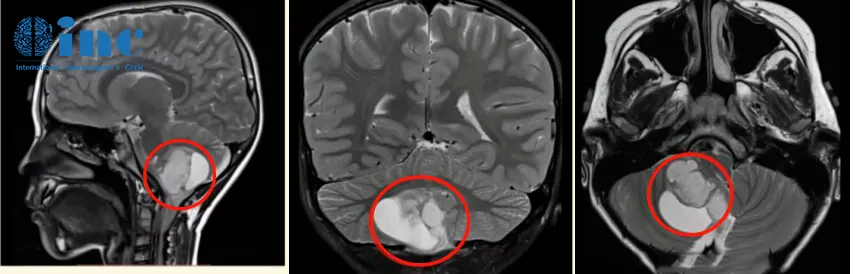

病史回顾:2020年末,6岁的辰辰(化名)在一场小小的交通事故后总是抱怨头晕,核磁共振结果显示“小脑占位”,右侧小脑半球见40mm*37mm大小异常信号,邻近四脑室受压变窄,脑干受压,中线结构局部左移。医生给出诊断,考虑可能是低级别的星形细胞瘤。

手术治疗:巴教授在详细分析辰辰的病情后表示,MR显示非常典型的小脑良性肿瘤,常见的是毛细胞性星形细胞瘤。患儿需要手术。完全切除肿瘤后,这个患儿几乎可以达到从肿瘤中康复。切除率必须达到100%,我将尽一切努力实现这一重要目标。

图4:术前术后影像对比。术后MR复查显示肿瘤全部切除,无残余,脑干得到充分减压,对中脑的挤压/移位压力明显减少,小脑复位。